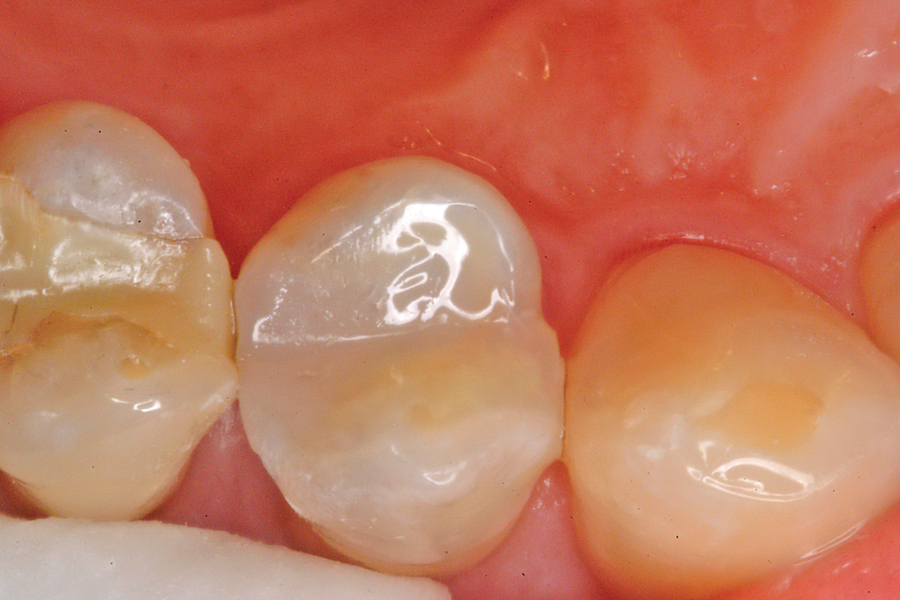

Figure 11. The completed Perimeter Restoration will now serve the patient effectively for many years.

The composite restoration is the basic foundation of the general dental practice. Countless composites are placed by dentists every day. Through the science of adhesive dentistry these restorations can be conservative and provide long term service. With time and function some breakdown may occur, usually at the margin of the restoration, the interface between tooth … Read more